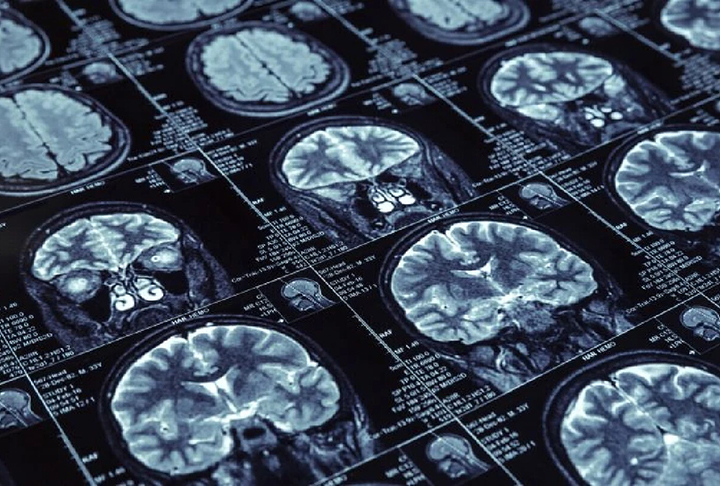

Mundo deve ter 139 milhões de pessoas com Mal de Alzheimer em 2050